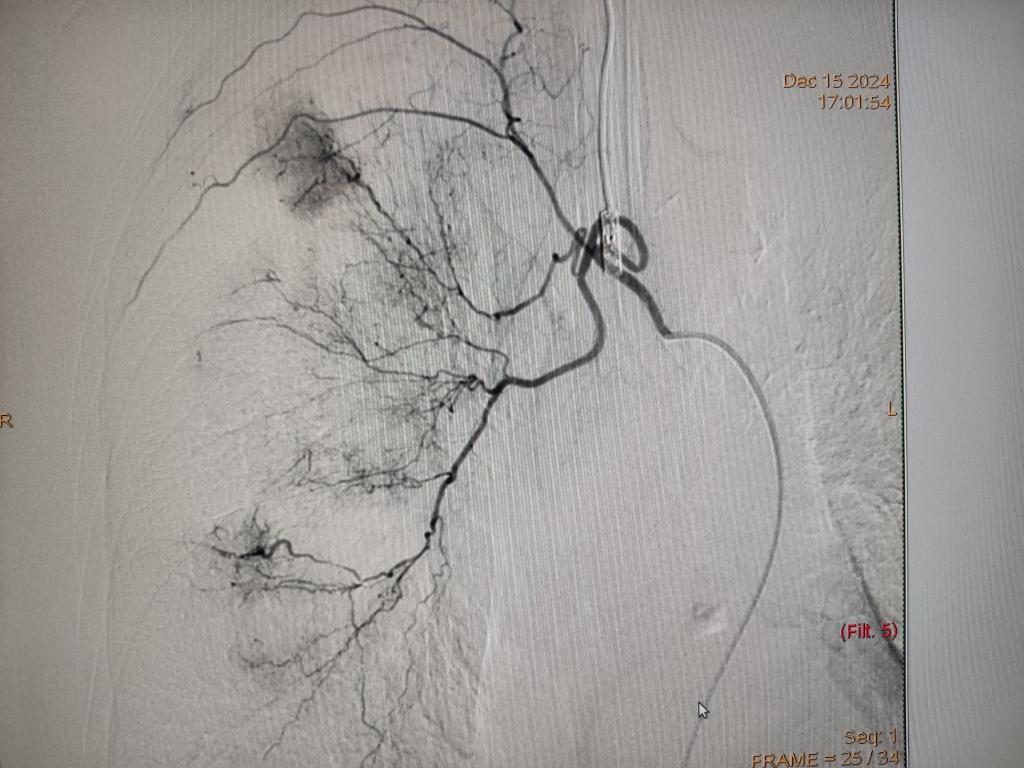

黄玲教授团队就咯血的介入治疗进行了讲解及相关手术直播演示,让参会者更加直观地了解了支气管动脉栓塞术的操作过程和技术要点。